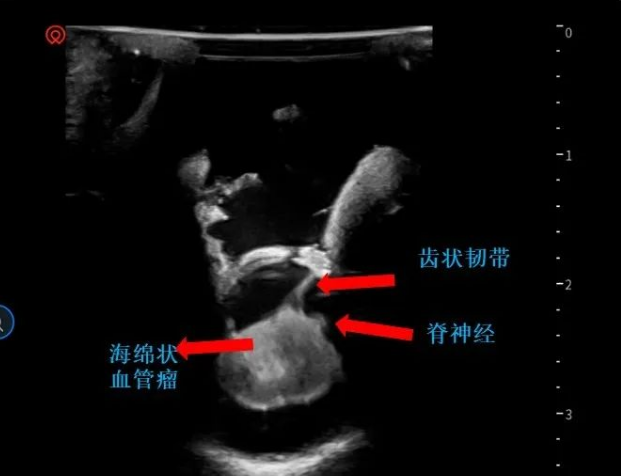

▼术中超声定位海绵状血管瘤(白色)

▼术中超声显示髓内海绵状血管瘤超出骨窗大小,向T7方向生长,继续磨除部分T7椎板,扩大暴露范围

半椎板切除术主要根据髓内海绵状血管瘤的定位选择患者位置,患者在俯卧位进行手术。医生在病变区域通过标准方法,即通过背根入口区或中线脊髓切开术接近深部病变。除了精确的定位和脊髓的较佳进入区域,解剖技术可能会影响髓内海绵状血管瘤的手术结果。手术过程中,使用双较钳和微型剪刀来断开引流血管是的重要。在确定手术平面后,应以锋利的解剖方式进行病灶切除,以避免损伤正常脊髓组织。

巴特朗菲教授指出,显微镜可用来顺利地进行髓内手术切除,当创口较小化并且在精确的肿瘤位置进行切除时,这些损伤通常不会在切除期间出血。术中神经监测对神经外科医生有很大帮助,使其能够更精确地操作并且术后神经功能缺损的风险更低。由于髓内海绵状血管瘤通常位于脊髓的背面,因此,我们证明术中SSEP监测是监测此病手术中脊髓完整性的可靠手段。